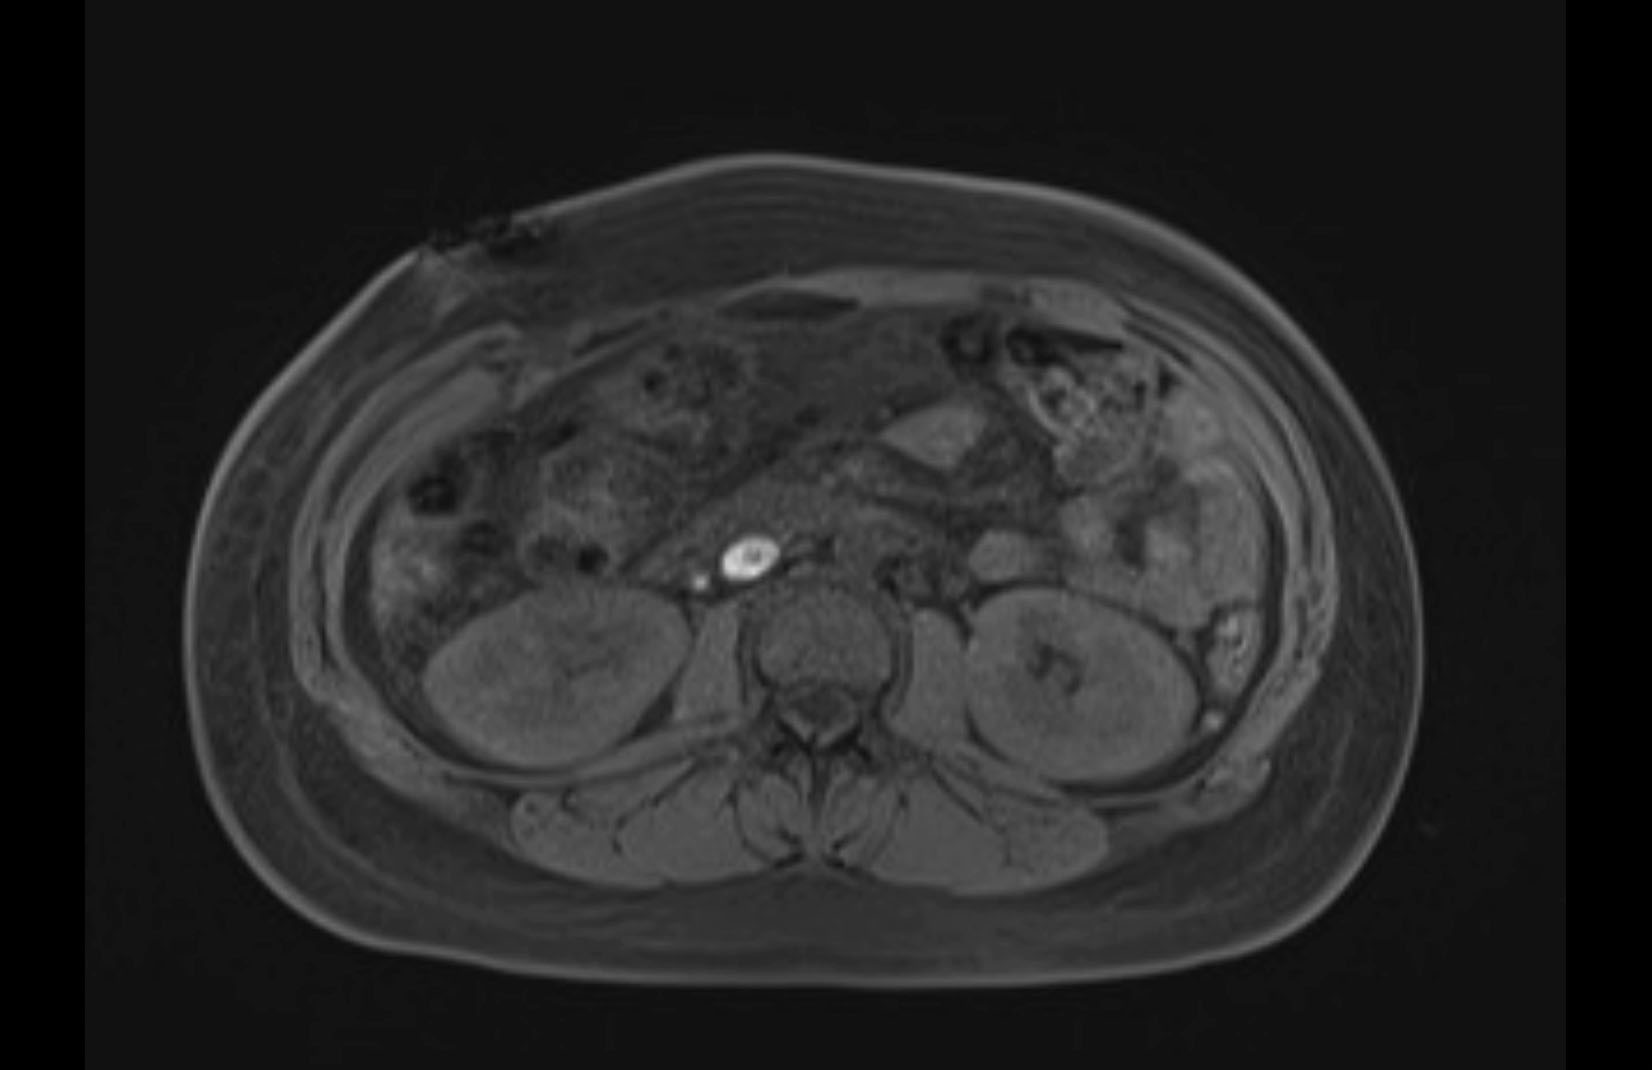

Imaging Analysis

Look through the patient's CT scan to identify any areas of concern for the necessary procedure.

MRI T1

MRI T2

Based on initial findings, which issue(s) would you be most concerned about?